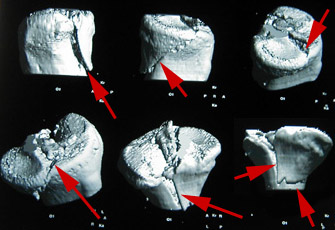

Auf dem Computertomogramm (3D-Rekonstruktion des Schienbeinkopfes bzw. Tibiaplateaus) sieht man schön die Bruchstelle des grossen Knochenfragmentes. Dummerweise geht der Bruch mitten durch die Kniegelenkfläche. Dazu kam noch ein sogenannter Impressionsbruch, hier nur für Profis erkennbar: Ein Teil der Gelenkfläche wurde durch die Gewalt des Sturzes in den Knochen hineingepresst.

Leider kommt das wegen der Beschaffenheit des Knochens nicht von selbst wieder hoch und musste angehoben sowie durch eine sogenannte Spongiosaplastik festgemacht werden (Knochenmaterial wurde aus dem Beckenkamm entnommen und im Knie unter das eingedrückte Stück wieder eingesetzt).

Als Vergleich: Wenn man den Finger in ein Stück Styropor drückt, bleibt auch ein Loch zurück. Dazu waren auch die Kreuzbandansätze angerissen.